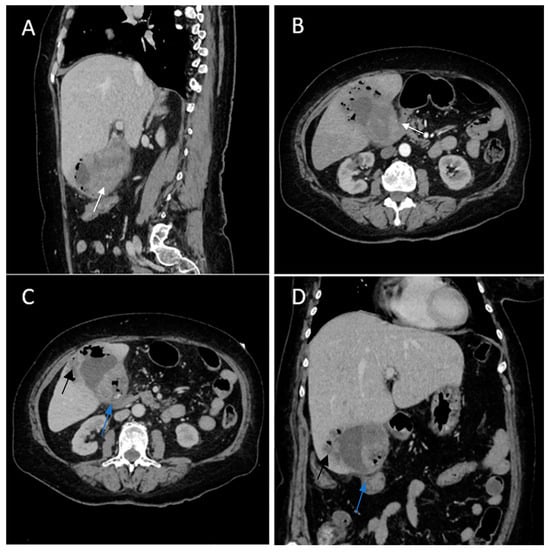

Biphasic (arterial phase followed by venous phase) contrast-enhanced emergency CT was performed (Figure 1), which clearly highlighted a gallbladder hydrops, with asymmetric, irregular gallbladder mural thickening, associated with multiple intraluminal mixed stones (Panel A). The tumoral mass extends directly into the adjacent liver parenchyma in segments IV and V and is in contact with the ascending colon (Panel C). Hepatomegaly can be observed (right hepatic lobe measures = 190 mm), with nodular lesions, disseminated in both hepatic lobes, hypodense, with rim peripheral contrast enhancement, more numerous in the right lobe, presenting various sizes (up to 35 mm in segment V) highly suggestive of liver metastases (Panel B and Panel C). Lymphatic metastases are common in gallbladder cancer. In this particular case, CT showed multiple lymph nodes enlargements in the hilar, mesenteric, celiac and precaval regions, up to 26/25 mm (measured in the hepatic hilum), with associated central necrosis (Panel D).

Figure 1. Multiplanar sections of contrast-enhanced CT acquisitions richly illustrating a low differentiated gallbladder adenocarcinoma. (A) Gallbladder hydrops (>40 mm transverse measurement, 142 mm longitudinal measurement) with asymmetric gallbladder mural thickening, 7 mm (white arrow), and multiple intraluminal mixed stones, 5–8 mm (black arrow). (B,C) Liver metastases—hypodense nodular hepatic lesions with rim contrast enhancement (yellow arrow). (C) Tumoral extension into IV, V segments of the right hepatic lobe and contact with the ascending colon (green arrow). (D) Lymphatic metastases (white stars).